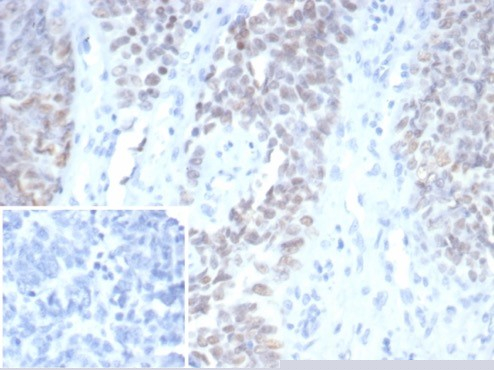

Formalin-fixed, paraffin-embedded human ovarian carcinoma stained with Wilm's Tumor Mouse Monoclonal Antibody (WT1/7450). Inset: PBS instead of primary antibody; secondary only negative control.